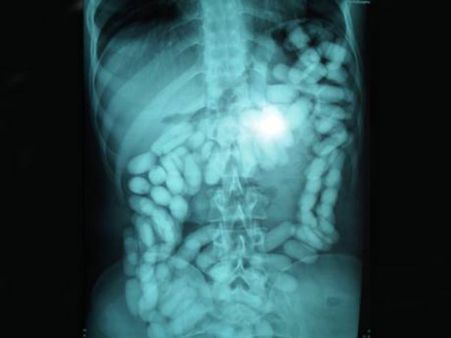

ড্রাগ

মেথামফেটামাইনের ৫২টি ক্যাপসুল পেটের ভিতর করে নিয়ে গিয়ে পাচার করতে যাচ্ছিল এক নাইজেরিয়ার ব্যক্তি। বিমানবন্দরে ধরা পড়ে সে। এরপর এক্সরে -তে যে ছবি সামনে এল তা ভয়ঙ্কর।